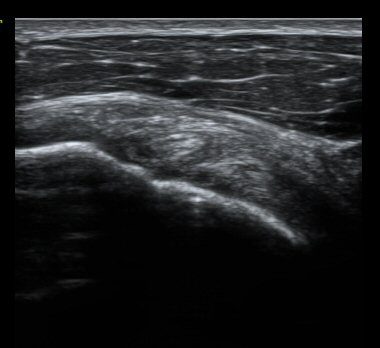

ȸÀü±Ù°³°£°Ý Ⱦ´ã³à°Ë»ç¿¡¼­ ƯÀÌ ¼Ò°ßÀ» º¸ÀÌÁö ¾ÊÀ½(±×¸² 1).